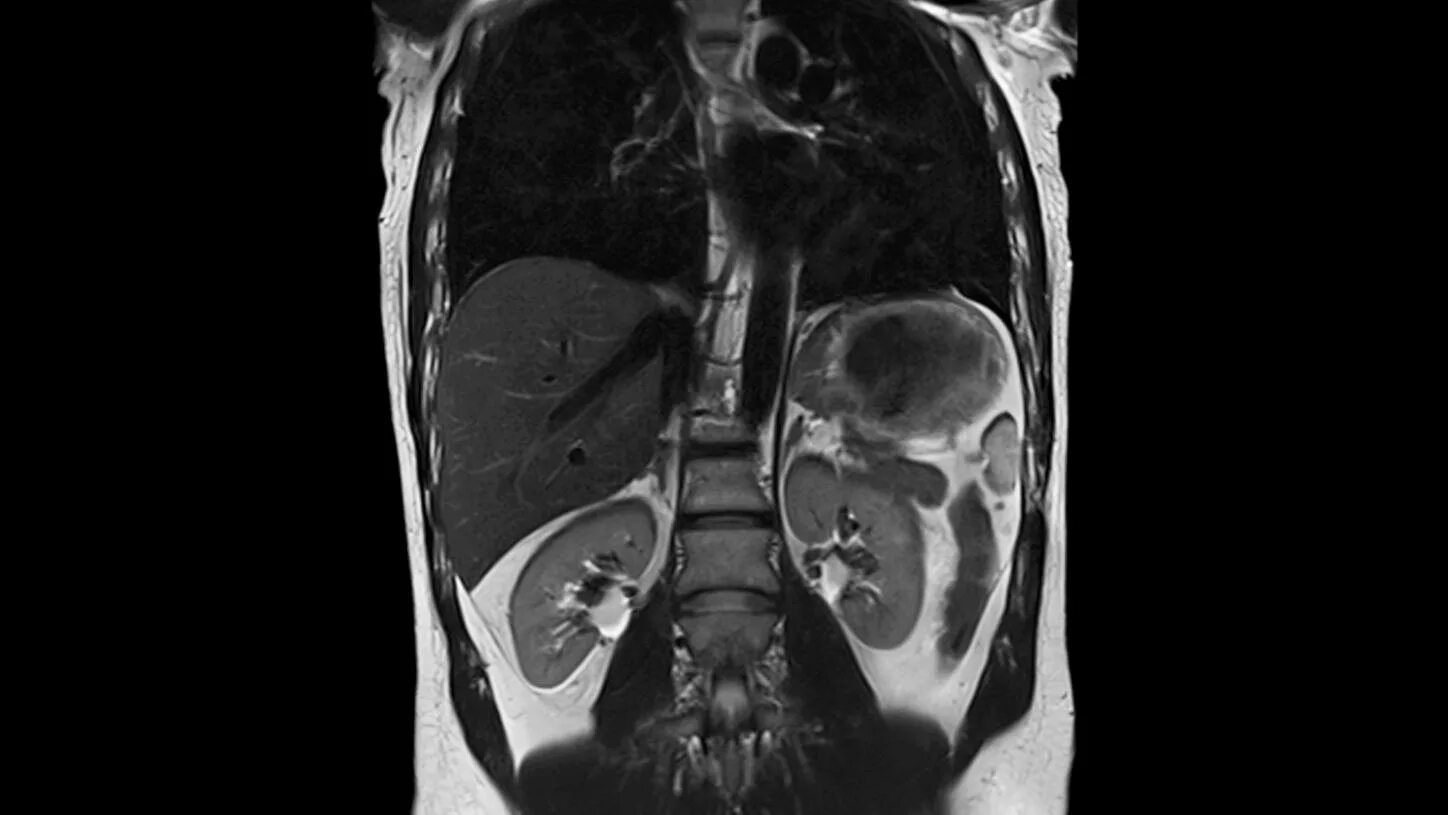

Что входит в мрт забрюшинного пространства